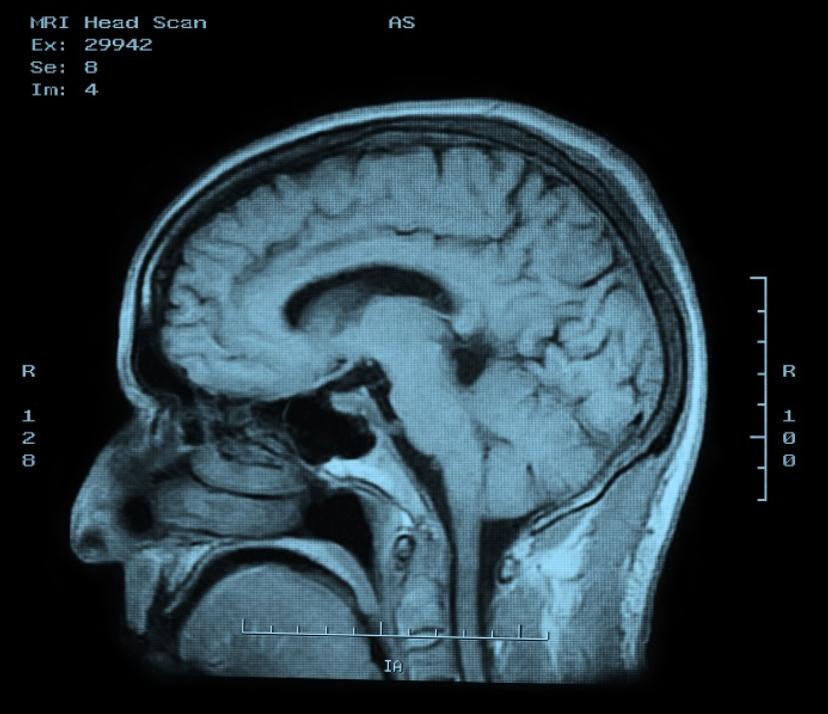

Definitive diagnosis of AD has traditionally relied upon post-mortem neuropathologic tissue analysis, requiring histological examination of brain tissue at autopsy, or in a rare case, following brain biopsy.3 Biomarkers are measurable proteins or genes in the body that relate to normal and abnormal processes within the body. In the case of AD, two biomarkers within the cerebrospinal fluid (CSF) can be measured to monitor Alzheimer’s disease progression—amyloid ß and tau proteins. It has been shown that the level of amyloid ß protein decreases during AD pathology.2